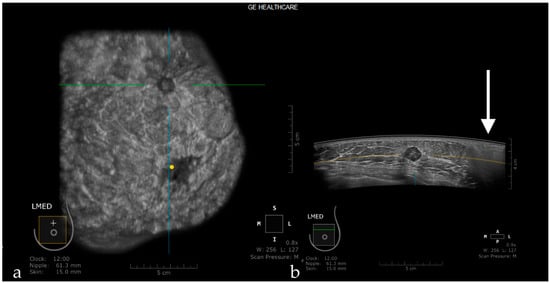

Attenuation Areas

Post-traumatic or post-therapeutic edema, or edema due to infectious or carcinomatous mastitis, causes the appearance of diffuse attenuation areas inside the glandular parenchyma (Figure 7).

Figure 7. Diffuse attenuation areas inside the glandular parenchyma due to post-therapeutic edema, visible on the coronal (a) and axial planes (b).